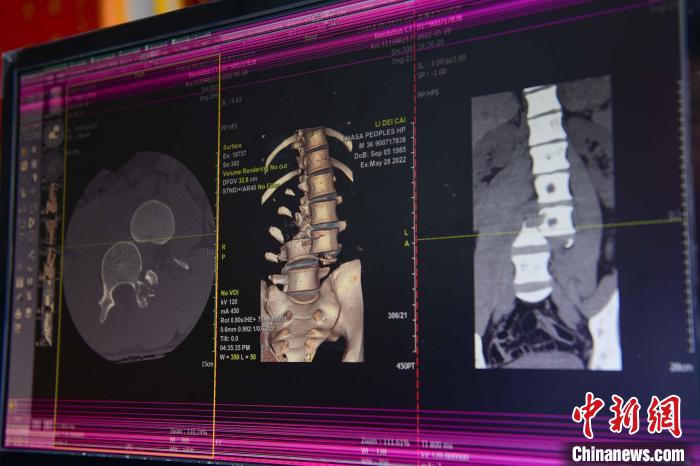

圖為患者術(shù)前,腰3/4脊柱骨折伴脫位。 扎西曲措 攝

通道開通后,拉薩市人民醫(yī)院完成了兩例脊柱創(chuàng)傷截癱患者的救治。一例23歲的病患為胸12椎體爆裂骨折伴截癱,另一例36歲的病患腰椎體骨折脫位伴雙下肢癱。按照脊髓損傷救治綠色通道流程,術(shù)前充分快速完善相關(guān)檢查,充分術(shù)前評(píng)估,向患者詳細(xì)交代手術(shù)風(fēng)險(xiǎn),入院當(dāng)天急診行手術(shù)治療。

北京“組團(tuán)式”醫(yī)療援藏專家、主治醫(yī)師何蔚介紹,兩名患者屬于脊柱骨折合并雙下肢截癱,手術(shù)十分復(fù)雜,需要快速且安全的完成手術(shù),在脊柱外科手術(shù)中屬于四級(jí)手術(shù),難度最高的一種。